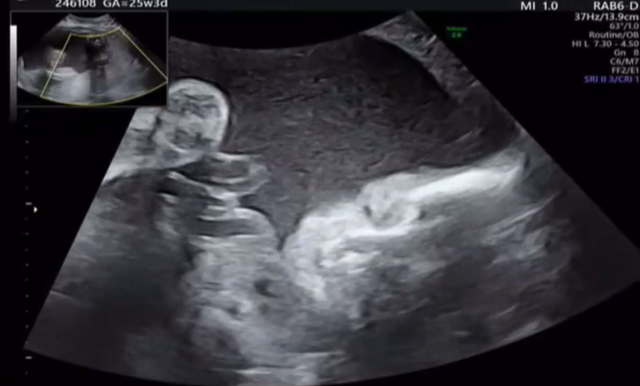

25w3d 妊婦健診✩